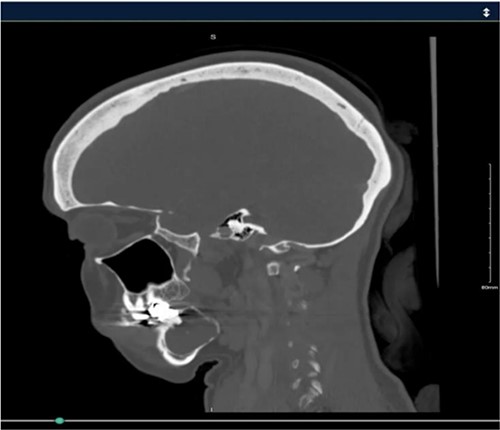

A 40-year-old woman presented with swelling on the right side of her mandible. She had completed orthodontic treatment 2 years earlier. A panoramic radiograph showed a unilocular radiolucency extending from the mandibular angle to the right first molar region (Figs 1–3).

Panoramic radiograph showing a unilocular radiolucency extending from the right mandibular angle to the right first molar region.

Panoramic radiograph highlighting the extent of the lesion from the mandibular angle to tooth #46.